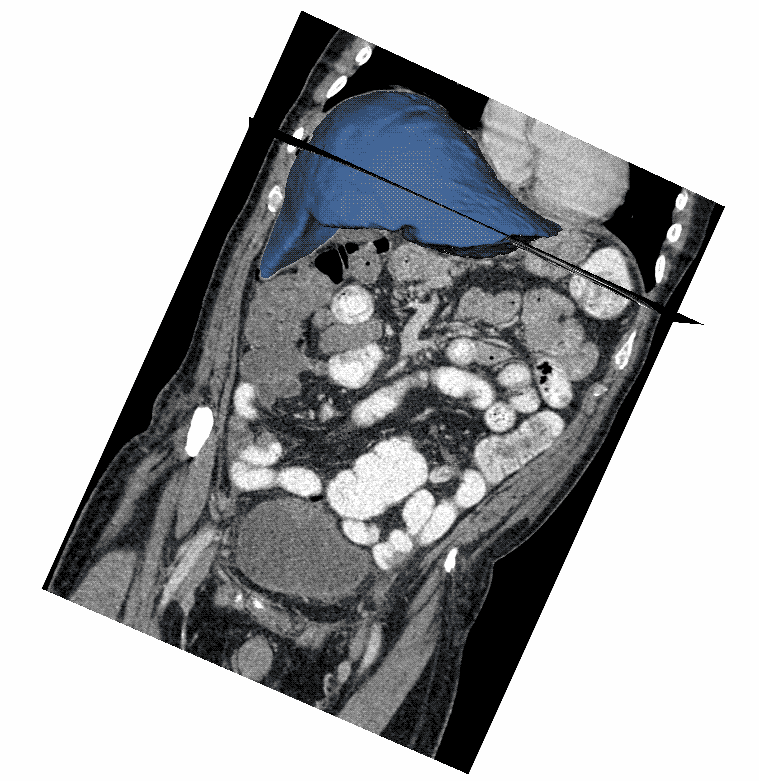

In the example below, we depict how our models work for a patient from the LiTS2017 test set (not used for training). Markedly emphasize that our algorithms automatically perform volume and RECIST measurements of the tumors. Moreover, using a function with an option to extend it to mRECIST the model make these measurements, if proper training data are available. What’s more, it can be a useful tool for monitoring patients in clinical studies.

Visualization: our algorithms work results

- Blue colour means: the liver segmentation

- Red colour means: the tumor segmentation

- White colour means: the RECIST measurements

- The models identified 4 measurable tumors with longest diameters of 26 mm, 18 mm, 16 mm, and 10 mm, and with corresponding volumes of 9 ml, 2.3 ml, 0.7 ml, 0.6 ml. For clarity, on the visualization we can see only two biggest lesions.